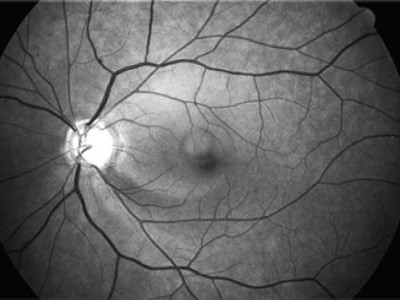

Současné zobrazovací metody glaukomu považujeme za velmi přínosné pro stanovení diagnózy glaukomu a sledování vývoje onemocnění v čase. Těmito metodami sledujeme objektivně projevy glaukomové neuropatie včetně její progrese.